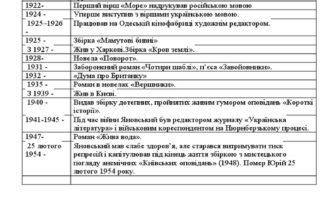

Наслідки видалення зуба мудрості

Тут веселіше, ніж здається: Відразу після процедур — це не мед на хліб. Спершу треба трохи пережити дискомфорт… або багато. Від болю до набряків — справжня одіссея.

- Біль і дискомфорт: Найпоширеніший наслідок — це біль. Іноді він настільки сильний, що не дає спокою кілька днів.

- Набряк: Виникає через втручання в тканини. З ним приходять проблеми з відкриванням рота.

- Інфекція: Найнебажаніший гість, але часом це реально.

- Кровотеча: Може тривати від кількох годин до цілої доби.

- Утворення сухої лунки: Відбувається, коли кров’яний згусток, що загрожує інфекцією, втрачається.

Коли варто турбуватись?

Навіть найсильніша біль лякає. Та є ситуації, коли слід забити на страх і з’явитися на консультацію:

- Якщо біль стає нестерпним і навіть ліки не допомагають.

- Якщо раптом з’являється гній.

- При підвищенні температури — це ніколи не добра прикмета.

- Настінний набряк не зменшується впродовж тижня.